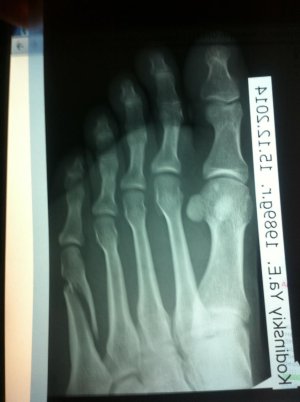

Получил перелом 5 плюсневой кости со смещением.

Ноложили временно гипс и мой доктор говорит что нужно хирургическое вмешательство

Такой вопрос: Нужно ли хирургическое вмешательство и какие могут быть последствия

без хирургического вмешательства

Фото прилагаю

IMG_3331.jpgIMG_3332.jpg

Трудно на основании скудной информации делать заключение. Возраст, как я понял молодой, перелому 5 дней. Формально можно без операции, срастется без последствий (стельки не забудьте после снятия гипса)